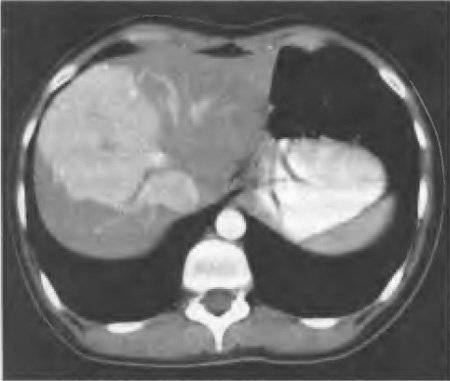

Рис. 59-5. Компьютерная томограмма (артериальная фаза контрастирования): фокальная нодулярная гиперплазия правой доли печени.

При ангиографическом исследовании также отмечается быстрое накопление опухолью контрастного вещества в артериальную фазу, опухоль имеет чёткие контуры.